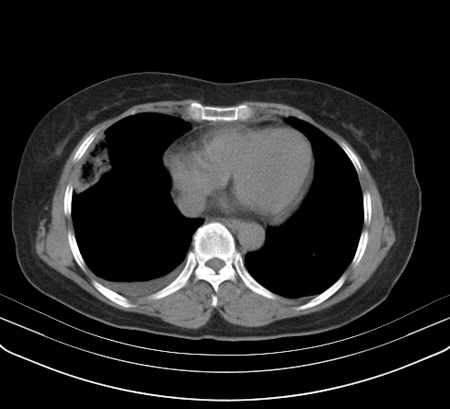

以下是引用余辉在2009-2-19 20:10:00的发言:[br]多考虑急性感染性病变,右中叶尚可见多枚小斑片状影,多为化脓性肺炎,双侧胸腔积液

以下是引用随光逐影在2009-2-19 20:33:00的发言:[br]1)考虑右肺炎症;建议抗炎治疗后复查。2)双侧胸腔积液(以右侧为甚)。

以下是引用花凤凰在2009-2-19 20:46:00的发言:[br]病人有发热,胸痛急性起病,主要病变位于右肺中叶外侧段,呈楔行改变,位于外带胸膜下,考虑为肺梗塞可能!!!!!!!!!!!!!!!!!!!!!!!!!!!!!!!!!!!